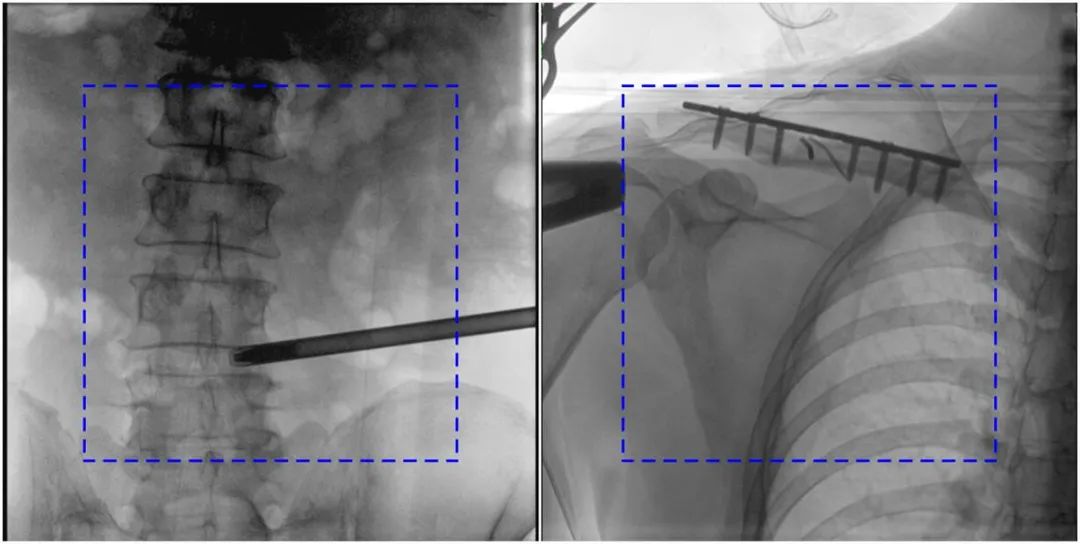

在進行髓內釘內固定術時,醫生需要同時觀察到入釘點和骨折部位的情況,普愛醫療大平板一體式C形臂采用30CM×30CM的平板探測器,能夠呈現更廣闊的成像面積,滿足大部分長骨髓內釘內固定術的攝片需求。

PLX119C臨床圖像與傳統圖像對比

注:藍色虛線內為傳統21CM×21CM平板的成像區域。